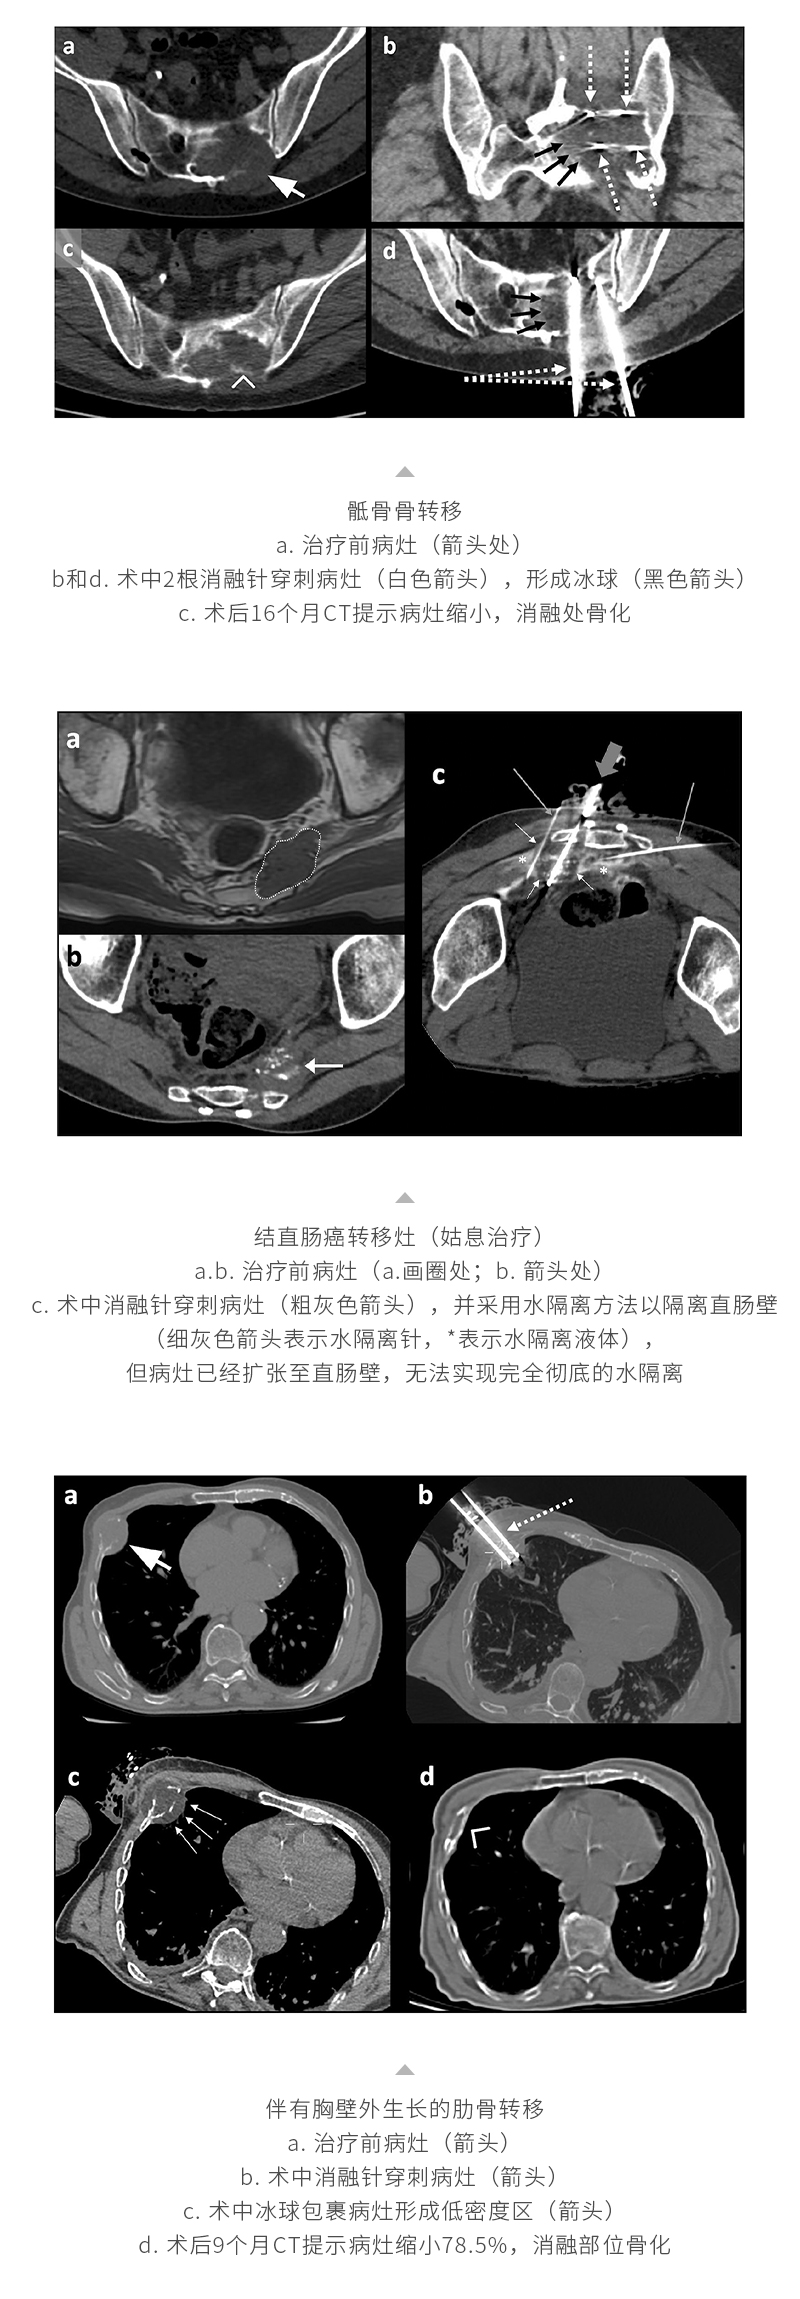

冷凍消融轉移性骨腫瘤——【海杰亞科研資訊】第268期